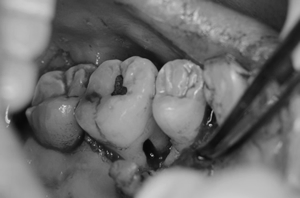

エルビウムヤグレーザーを使い再生療法をしました。 |